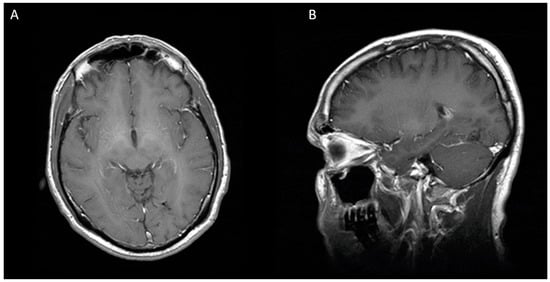

Figure 3.

Eight months after second stereotactic needle aspiration, MRI is showing a complete resolution of cerebral abscess. (A) Axial view (B) Sagittal view.